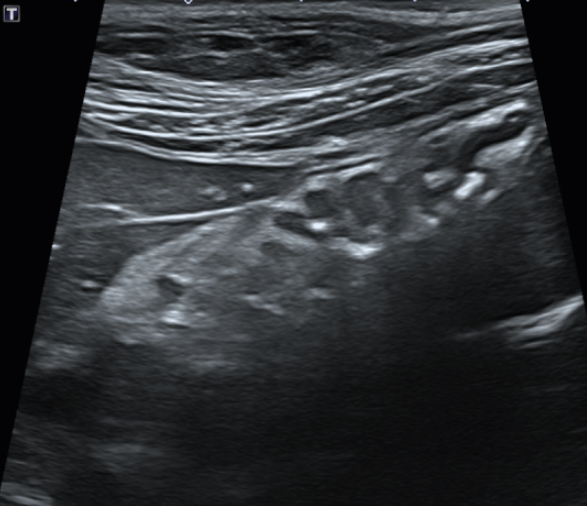

이물 제거 후 초음파 검사 실시 결과 이물이 완전히 제거된 모습입니다.